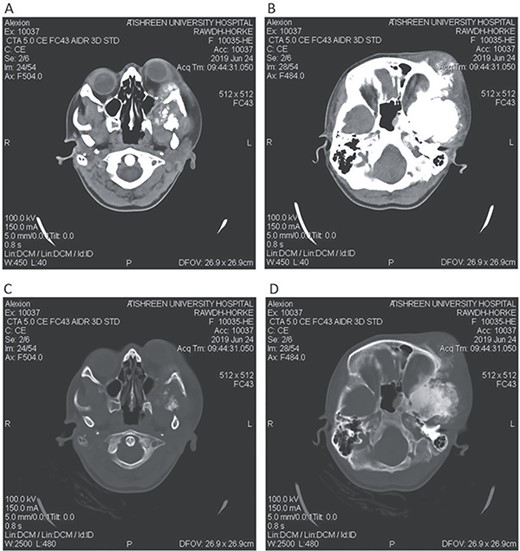

CT head bone window (A–C). A. Invasion of the frontal bone. B. Invasion of the orbit. C. Invasion of the parietal bone. D. Invasion of the sphenoid, temporal and parietal bones.

A 17-year-old female presented with a history of osteosarcoma that was confirmed after undergoing a surgery to remove an enlarging bone tumor in the left temporal region 2 years ago. She later got pregnant and delivered her child but never got back for a checkup until she was admitted to our hospital with a severe and unresponsive to medication headache that progressed over the course of 6 months and blurred vision that progressed to complete left-sided vision loss. Physical examination revealed a tough and mobile yet fixed at the base 7-cm mass towards the left of the frontal bone. Many more masses were revealed in the left side of the skull including the anterior cranial fossa, orbit, base of the skull and the left part of the occipital region where the previous procedure was performed (Fig. 1). These masses had been increasing in size probably under the influence of pregnancy hormones causing pain that radiated along the orbital and maxillary branches of the left trigeminal nerve. Physical examination and past medical history were otherwise unremarkable. Laboratory tests were all normal, and her family history was negative. Staging studies showed no evidence of distant metastatic disease in the chest, the abdomen and the pelvis. CT scan of the skull revealed a bone-forming non-lytic lesion accompanied by periosteal reaction. This lesion bulges to the outside towards the scalp spreading into both the soft tissues and the inside of the entire left side of the skull with a sunburst-pattern (Figs 2 and 3). Its rims are unsymmetrical and pointy, and it bulges into the left orbit outside the muscles causing exophthalmos with a semi-complete proptosis of the eyeball out of the orbit (Figs 2 and 3). This lesion applies pressure to the left frontal and temporal lobes causing mild edema in both these lobes without invading the brain tissue. This edema in turn applies pressure to the left lateral ventricles (minor shift of the elements of the midline to the right side can be seen on CT) (Fig. 4). Due to the tumor’s wide spread, the surgical procedure was performed in two stages (approximately 6-hour-long each). In the first stage, the bone mass was removed through a procedure of wide skull approach including the frontal, temporal and parietal bones and a removal of the invading part of the temporal muscle. Moreover, the lateral wall and roof of the left orbit were removed, the left optic nerve was dissected free and part of the meninges was removed and replaced with an autogenic patch from the fascia lata. Then, the bone loss was compensated for by using bone cement Synicem VTP (poly methyl methacrylate and Barium sulfate), and the orbit was rebuilt; the eyeball was placed back with noticeable decline of the exophthalmos. In the second stage, a complementary left parietal occipital incision of the previous approach was performed 3 weeks later; the remaining of the frontal and occipital bones was removed, and a partial mastoid surgery was done. Furthermore, the cavernous sinus were revealed and found to be not invaded. Later on, the normal skull shape was restored using the same cement. The histopathology of the lesion revealed proliferation of neoplastic chondroblasts, osteoblasts and spindle-shaped cells. The features are consistent with low-grade chondroblastic osteosarcoma (Fig. 5). The patient did not need ICU admission. She recovered well 3 days after the surgery and was discharged with no deficits. A CT scan that was performed post-operatively revealed that the masses were successfully excised (Figs 6 and 7). At the last follow-up 1 month post-operation, the patient was scheduled to undergo a course of radiotherapy, 60 Gy of radiotherapy in 30 fractions over 4 weeks without chemotherapy, as it is not recommended with low-grade osteosarcoma.